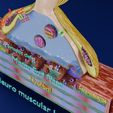

神经肌肉接头示意图